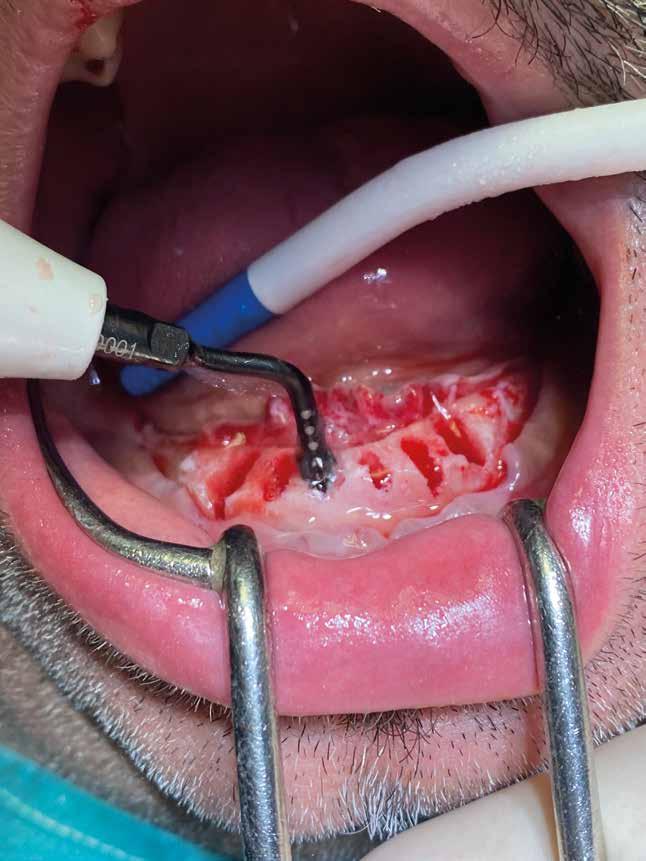

1. Accessi chirurgici (Figg. 1,2)

Esempio chirurgico di accesso tra 2 elementi dentari con conformazione della cresta alveolare ampia. Incisione del lembo in cre sta senza scarichi laterali con sollevamento di 2 lembi, palatale e vestibolare; si può notare come quest’ultimo non si estenda oltre

Un ridotto scollamento dei tessuti molli riduce edema e dolore post operatorio, mentre la preparazione del sito implantare a bassi giri con irrigazione limita il trauma del tessuto osseo.

La microvibrazione degli inserti ultrasonici non presenta la tendenza allo scivolamento tipica delle frese rotanti consentendo di mantenere con maggiore semplicità e precisione l’orientamento del tunnel implantare, soprattutto quando si prepara all’interno dei un alveolo post-estrattivo agendo su una superficie liscia e inclinata. Nelle immagini è possibile vedere una serie di situazioni in cui

Una pulizia approfondita e delicata può essere effettuata con il piezo-clean anche su piani ossei coinvolti dalla chirurgia resettiva. Lo strumento crea una zona circoscritta di applicazione di ultrasuoni amplificando l’azione di detersione dei residui di tessuto necrotico, di microorganismi patogeni e di vasocostrizione, che migliora la visibilità del sito.